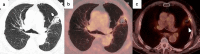

Image-guided percutaneous lung ablation has proven to be a valid treatment alternative in patients with early-stage non-small cell lung carcinoma or oligometastatic lung disease. Available ablative modalities include radiofrequency ablation, microwave ablation, and cryoablation. Currently, there are no sufficiently representative studies to determine significant differences between the results of these techniques. However, a common feature among them is their excellent tolerance with very few complications. For optimal treatment, radiologists must carefully select the patients to be treated, perform a refined ablative technique, and have a detailed knowledge of the radiological features following lung ablation. Although no randomized studies comparing image-guided percutaneous lung ablation with surgery or stereotactic radiation therapy are available, the current literature demonstrates equivalent survival rates. This review will discuss image-guided percutaneous lung ablation features, including available modalities, approved indications, possible complications, published results, and future applications.